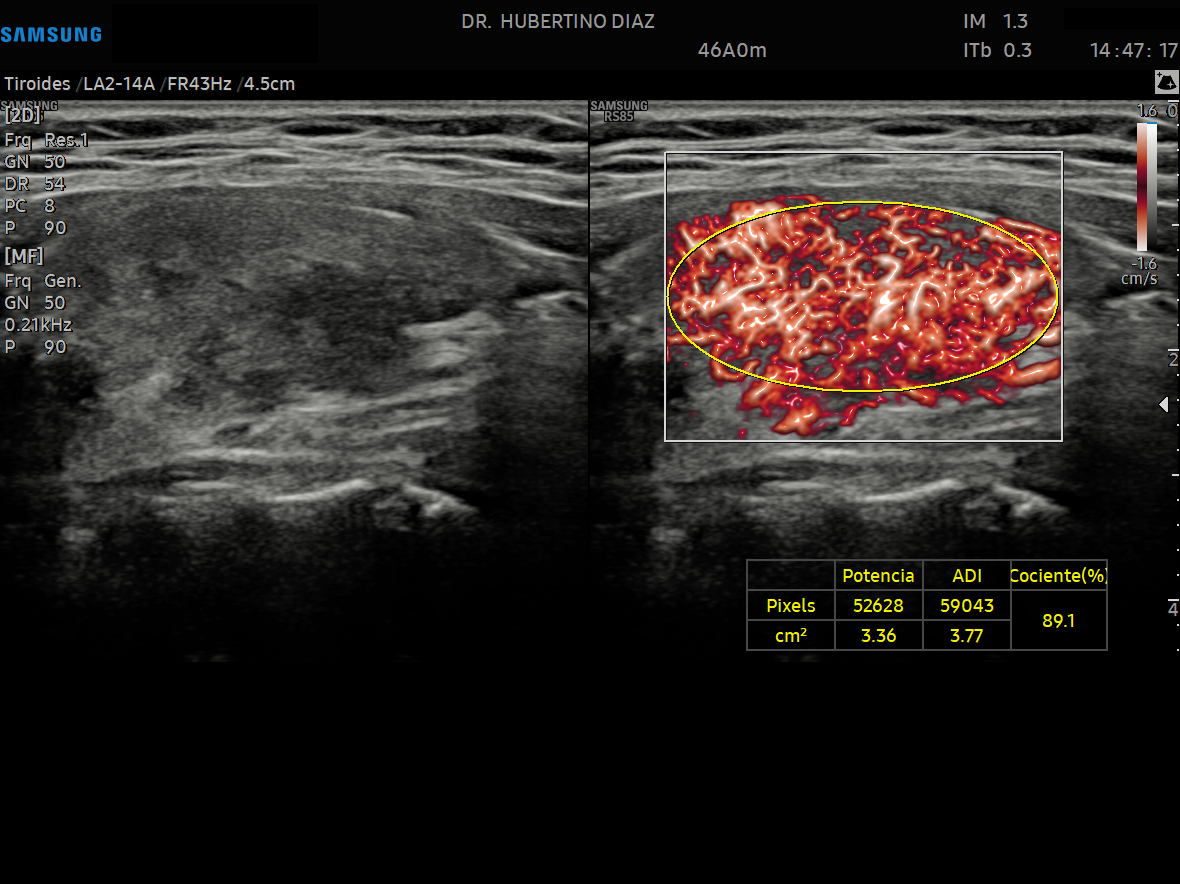

ECOGRAFÍA DOPPLER DE TIROIDES

El estudio Doppler es un parámetro de evaluación de suma imp...